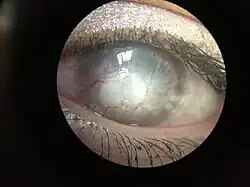

| Complete corneal opacity in right eye with normal left eye | |